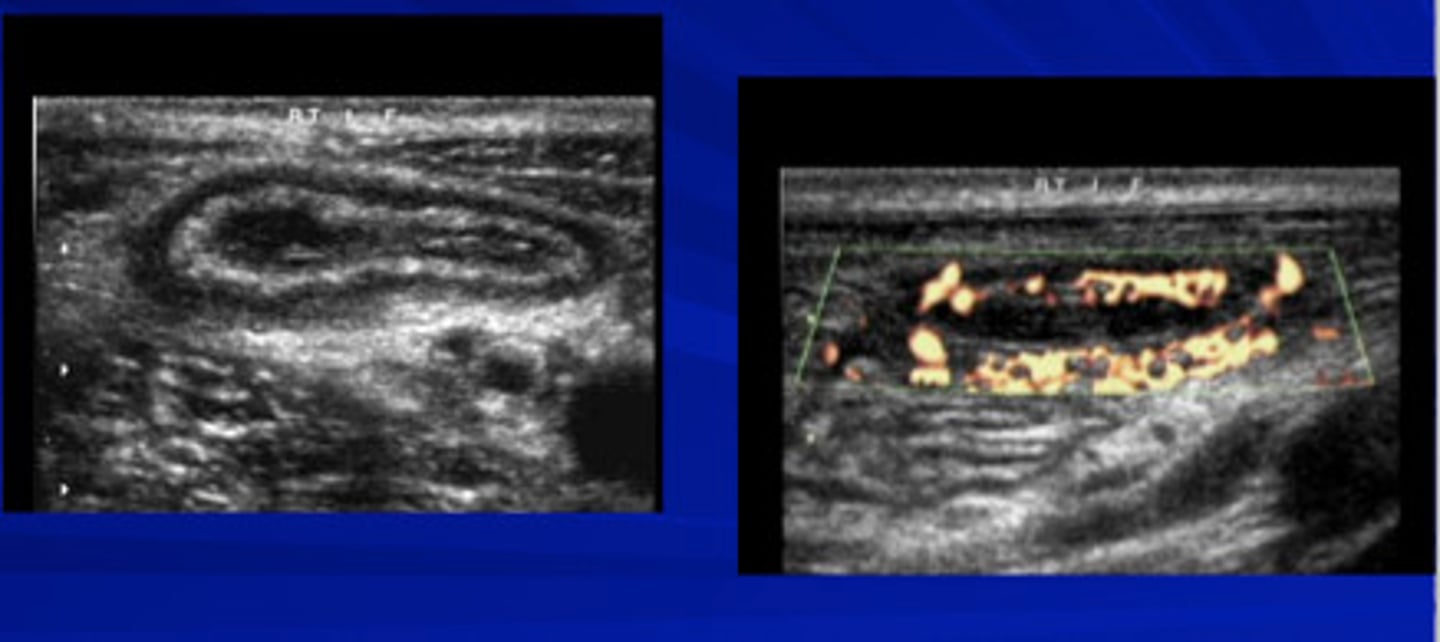

What is hypertrophic pyloric stenosis? What are some s/sxs?

Hypertrophy of pylorus muscle resulting in gastric outlet syndrome; projectile non-bilious vomiting followed by a desire to feed (nothing is getting past), dehydration (sunken fontanelles), palpable olive-like mass in the epigastric/RUQ area

What is best initial & best overall test to diagnose hypertrophic pyloric stenosis? What will be seen?

Initial: abdominal US

Best: upper GI contrast series - string/apple core sign